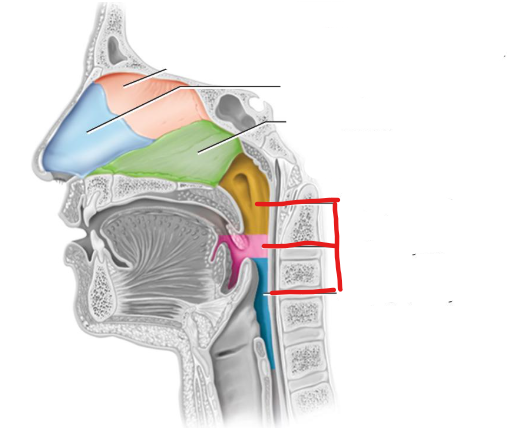

What structure is this?

The nasopharynx region of the pharynx

What structure is this?

The Oropharynx region of the pharynx

What structure is this?

The Laryngopharynx region of the pharynx

The pharynx